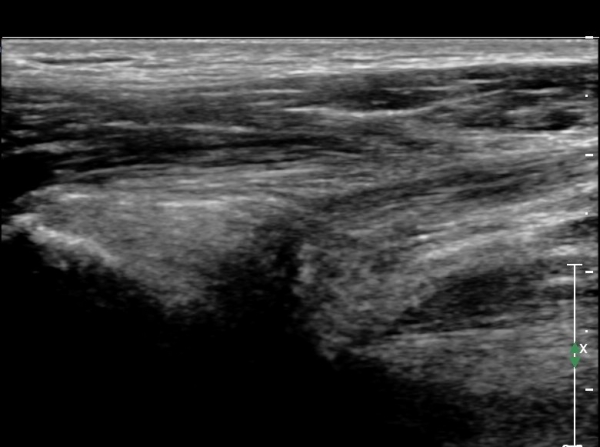

°í°üÀý À§, ¿ÜÃø¿¡¼­ ´ëÅðÁ÷±Ù Á¾´Ü¸é°Ë»ç»ó  ´ëÅðÁ÷±Ù °ðÀº ¼¶À¯(direct) ±â½ÃºÎ¿¡ ¹Ì¼¼ÇÑ

¼®È¸¼º º´º¯À» º¸À̳ª ÈûÁÙÀÇ Àú¿¡ÄÚ ºÎÁ¾Àº °üÂûµÇÁö ¾ÊÀ½.(»çÁø 3, 4)